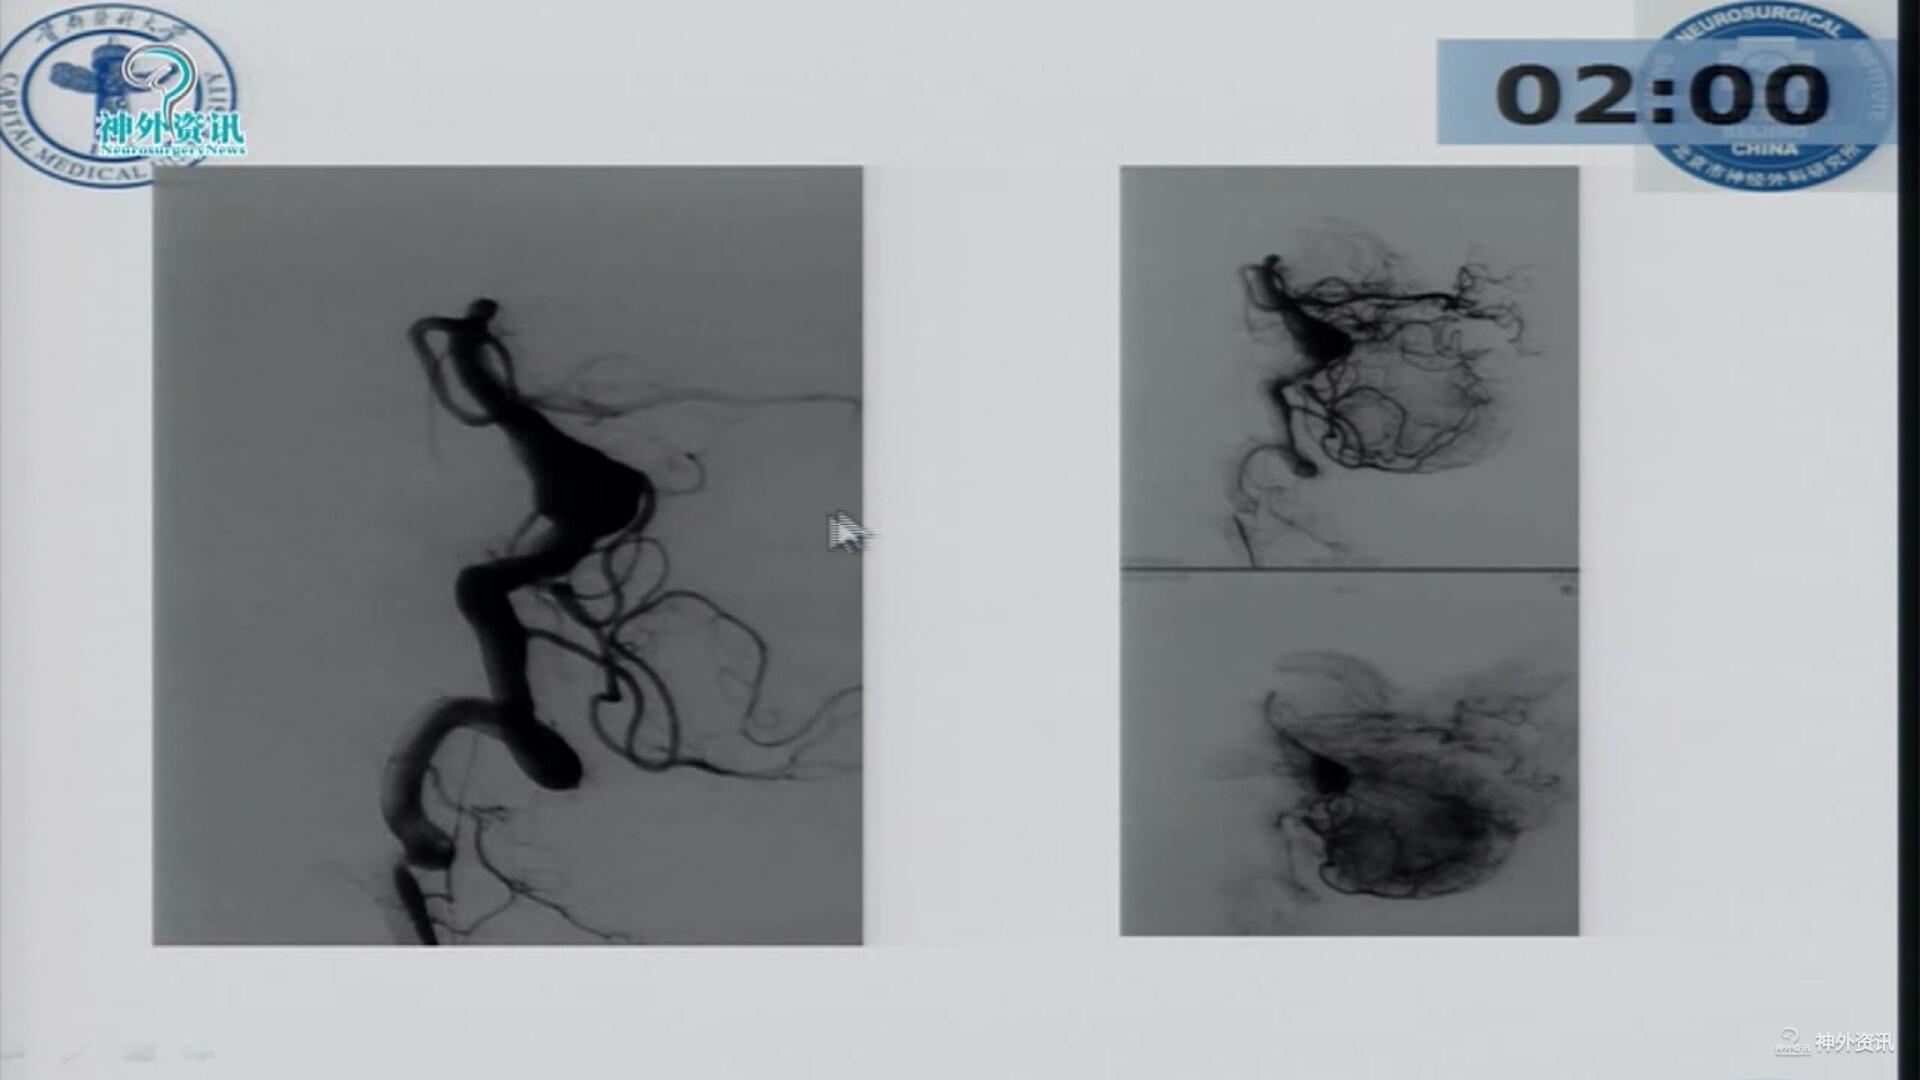

杨新健教授:颅内梭型及夹层动脉瘤的分型